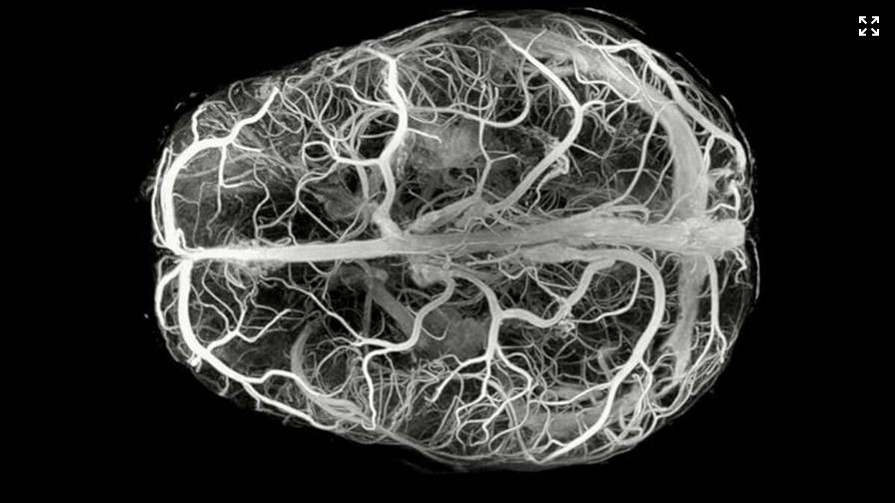

"Es un tipo de enfermedad que afecta a la sustancia blanca del cerebro y estos pacientes tienen problemas al andar, cognitivos, de desarrollo o dismorfia facial", ha explicado a EFE la directora del departamento de Neurometabolismo en Idibell, Aurora Pujol.